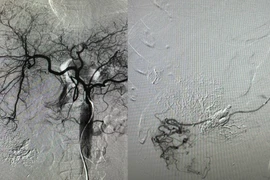

Nút mạch cứu người đàn ông vỡ u gan phức tạp máu chảy ồ ạt trong ổ bụng

Thời gian vừa qua, bệnh viện đã thực hiện cấp cứu nhiều người bệnh u gan vỡ do từ chối điều trị, xin về uống thuốc nam.

Nút mạch kết hợp đốt sóng cao tần RFA điều trị cho người bệnh có 2 khối u gan

Nút mạch u gan và đốt sóng cao tần (RFA) trong điều trị ung thư gan đã giúp bệnh nhân ung thư tránh được những ca phẫu thuật mổ mở, rút ngắn thời gian hồi phục.

Nút mạch cứu sống người đàn ông sốc mất máu do vỡ u gan

Nút mạch cầm máu trong điều trị u gan vỡ là giải pháp tối ưu cứu sống người bệnh bởi ưu điểm ít xâm lấn, bảo tồn gan, ít biến chứng, giảm tỷ lệ tử vong.